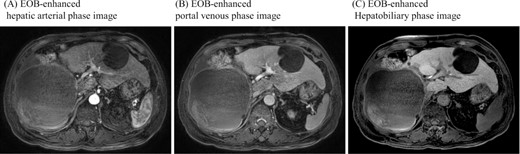

On referral to our hospital, his vital signs were within normal limits. The abdominal examination revealed rebound tenderness in his right upper quadrant region. There was no abdominal distension. The initial laboratory tests demonstrated a normal hemoglobin (10.2 g/dl) and elevated C-reactive protein levels (9.6 mg/dl). The results of serum tumor markers were as the follows: CA19-9, 193 784.3 U/ml; carbohydrate antigen 125 (CA125), 91.6 U/ml; carcinoembryonic antigen (CEA), 2.1 ng/ml; α-fetoprotein (AFP), 3.0 ng/ml; des-γ-carboxy prothrombin (DCP), 19 mAU/ml (Table 1). Dynamic CT showed a large cystic lesion (17 cm × 14 cm × 12 cm) in the right liver and discontinuation of the cystic wall and retention of ascites mainly the right subphrenic region (Fig. 1). T2-weighted single shot turbo spin echo magnetic resonance imaging (MRI) showed a-low intensity region with dorsal predominance in the high-intensity area and fluid–fluid level (Fig. 2). Gadoxetic acid (Gd-EOB) enhanced MRI didn’t show any lesion suggesting mural nodule in the cystic wall in any phase (Fig. 3). Paracentesis showed bloody fluid and the tumor marker levels in the sampled ascites were as the follows: CA19-9, 2 672 400.0 U/ml; CA125, 2618.9 U/ml; CEA, 41.7 ng/ml; AFP, 1.4 ng/ml; and DCP, 10 mAU/ml (Table 1). Cytology of the ascites showed no findings of malignancy.

Gadoxetic acid (EOB) enhanced MRI didn’t show contrast effect with a cystic lesion in any phase.